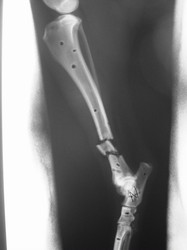

Fijación Externa

PRÁCTICAS CURSO DE FIJACIÓN EXTERNA PERFECCIONAMIENTO.

Híbrido.